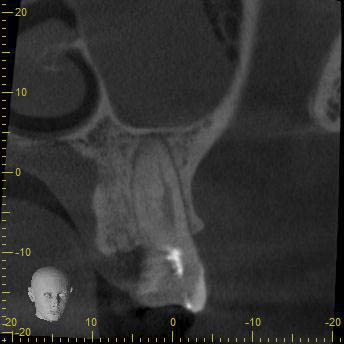

BN2627_DVT (12 von 17) Veröffentlicht 1. Dezember 2014 am 344 × 344 in Unerwartete Anatomie Zahn 26, 27- die WF